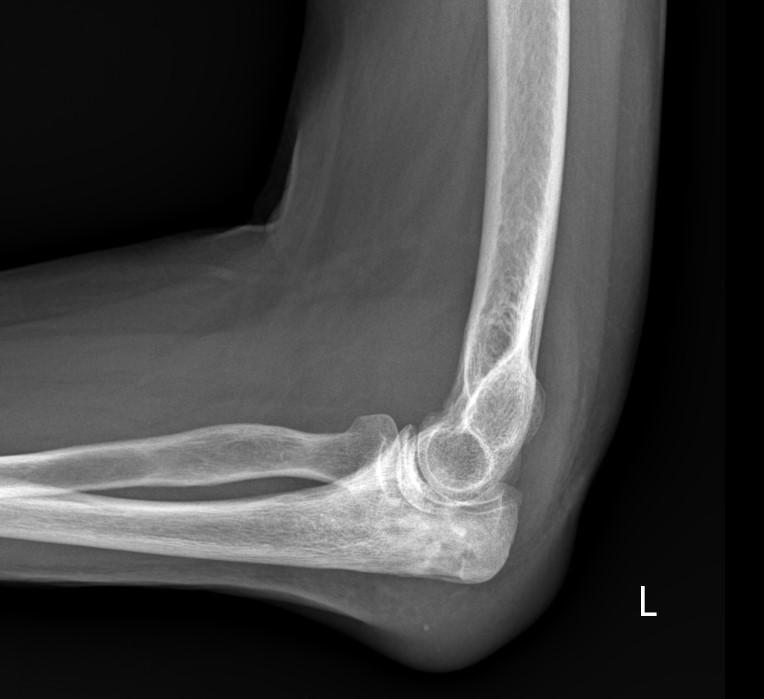

- рентгенография локтевой кости в двух проекциях — выявляет очаги остеолиза, периостит, секвестры (на поздних стадиях);

Рентгенологическая диагностика остеомиелита локтевой кости направлена на выявление признаков гнойно-деструктивного воспаления костной ткани, включая участки остеолиза, периостальной реакции и формирование секвестров. Исследование проводится в прямой и боковой проекциях в режиме обзорной рентгенографии с прицельной съёмкой предплечья, охватывающей весь объём локтевой кости.

Рентген выявляет следующие анатомические признаки:

- В прямой проекции при обзорной рентгенографии определяется зона пониженной рентгеновской плотности в диафизе или метафизе локтевой кости с размытыми контурами, свидетельствующая об участке остеолиза, часто сопровождающаяся очагами периостального наслоения.

- На боковой рентгенограмме визуализируется утолщение кортикального слоя с многослойной или гладкой периостальной реакцией, участками неравномерной плотности и признаками склерозирования окружающей костной ткани.

- При прицельной съёмке выявляется образование секвестральной полости с фрагментами костных секвестров, не соединённых с основной костью, а также возможное наличие свищевых каналов и признаков хронического течения.

Рентгенографическое исследование позволяет детально визуализировать следующие диагностические параметры остеомиелита локтевой кости:

- Размер и протяжённость очагов деструкции костной ткани, включая выраженность остеолиза и его границы в продольной и поперечной плоскости.

- Наличие и характер периостальной реакции, отражающей стадию воспалительного процесса и тип компенсаторного костеобразования.

- Выраженность склеротических изменений по периферии очага, указывающих на хронизацию воспалительного процесса и ограничение патологической зоны.

- Признаки формирования секвестров: чётко очерченные плотные участки, отделённые от основной костной структуры, служащие критерием зрелого остеомиелита.

- Состояние окружающих костных структур, включая возможное вовлечение лучевой кости или суставных концов при распространении процесса.